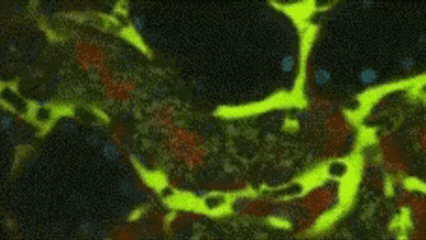

Renal capillaries with reduced blood flow caused by AKI (1)

Renal capillaries with normal blood flow

Human Kidney Perfusion Flow Before and After Treatment With RESTARI's Device